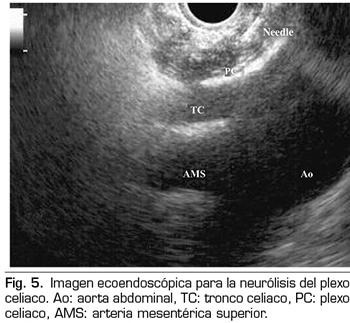

NEURÓLISIS ECOENDOSCÓPICA DEL PLEXO CELIACO

La ecoendoscopia ofrece la ventaja de una mayor visualización del plexo celiaco a corta proximidad, permitiendo una mayor precisión y seguridad en la administración del agente neurolítico y evitando la inyección en estructuras vasculares mediante el uso del Doppler (37) (Figura 5). No obstante, los trabajos que apoyan la neurólisis ecoendoscópica, considerada al igual que la técnica percutánea como una terapia de rescate, están limitados a estudios retrospectivos no controlados (38). Pauli y cols. publicaron un metanálisis que concluye que esta técnica consigue una reducción del dolor del 80 % en pacientes con cáncer de páncreas (39). Algunos estudios muestran un ligero descenso en el consumo de opioides, pero sin una fuerte evidencia científica.

En cuanto a los efectos adversos, se limitan a una serie de publicaciones retrospectivas y series de casos, estando descritos la hipotensión (11 %), la diarrea (18 %) y el dolor abdominal transitorio (1,5 a 8 %) (37). Teóricamente, esta técnica es más segura, con su abordaje anterior a través de la pared gástrica y paso directo de la aguja al plexo visualizando los vasos, sin tener que atravesar el espacio retrocrural (41). Aun así, también se han publicado complicaciones fatales con esta técnica. Gimeno-García y cols. (42) describieron la primera complicación de trombosis y vasoespasmo de la arteria celiaca que produjo una isquemia multiorgánica y la muerte del paciente. Desde entonces esta complicación se ha publicado en otros 2 trabajos, que también acabaron en muerte (43,44). Otros efectos adversos descritos son el sangrado retroperitoneal y 2 casos de paraplejia.

Dentro de las contraindicaciones relativas a esta técnica se encuentran: la presencia de varices gástricas o esofágicas −ya que aumentan el riesgo de sangrado−, una anatomía desestructurada, la invasión tumoral directa del plexo, y las malformaciones congénitas del tronco celiaco o de la arteria mesentérica superior.